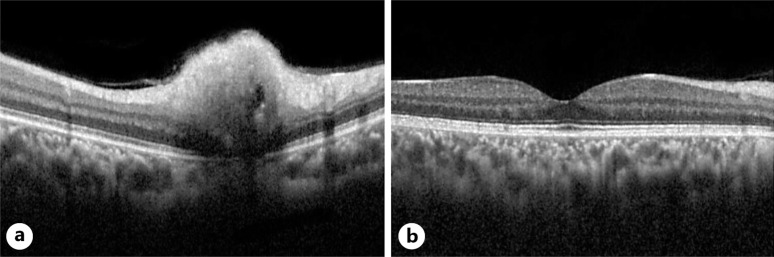

Introduction: Coexistence of optic disc hemangioma and pituitary gland cyst is a rare clinical scenario. Usually, a retinal capillary hemangioma or juxtapapillary hemangioma is associated with VHL syndrome. This case emphasizes the clinical presentation, diagnostic approach, and implications for patient care.

Case presentation: We report a case of a young patient, who came for a routine eye examination and got diagnosed with optic disc hemangioma incidentally. A complete systemic workup was done to rule out VHL syndrome during which MRI brain surprisingly revealed a pituitary gland cyst. The patient was referred to a neurosurgeon and observation was recommended as he was asymptomatic.

Conclusion: This case demonstrates how a good clinical examination, prompt documentation, regular follow-ups, and appropriate imaging facilitated the early diagnosis of both the optic disc capillary hemangioma and pituitary gland cyst. Consequently, this report also shows the importance of multimodal imaging in these young patients to detect these potentially life-altering conditions.